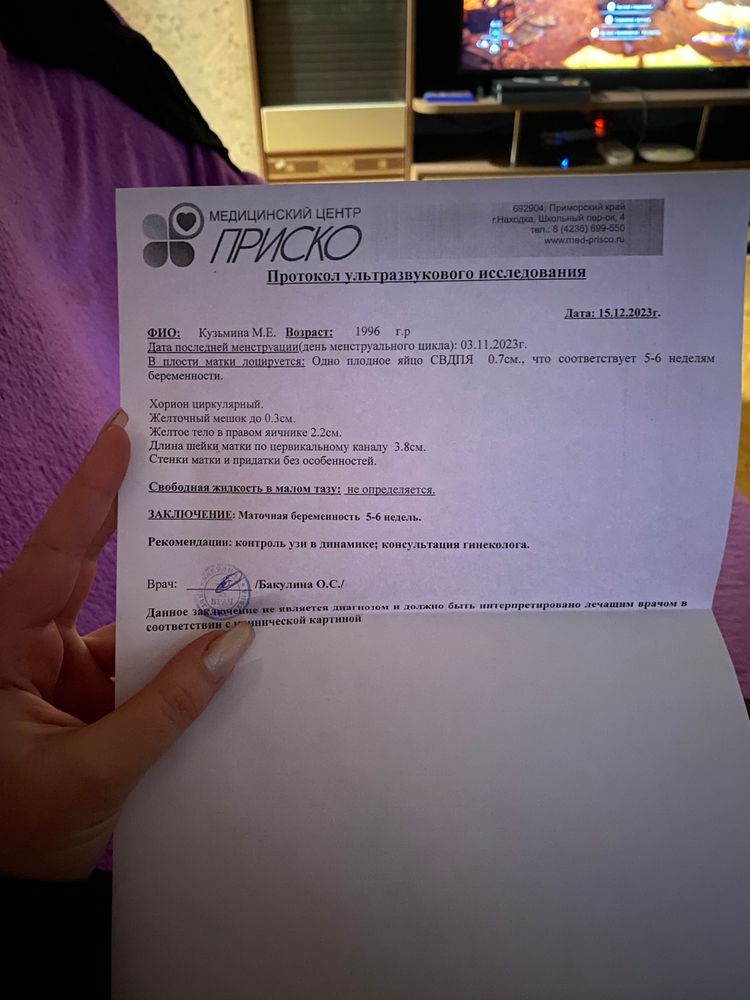

Это были мои 5,3 акушерских💁🏼♀️Второй раз уже пошла на 1 скрининг и всё ок

Это были мои 5,3 акушерских💁🏼♀️Второй раз уже пошла на 1 скрининг и всё ок